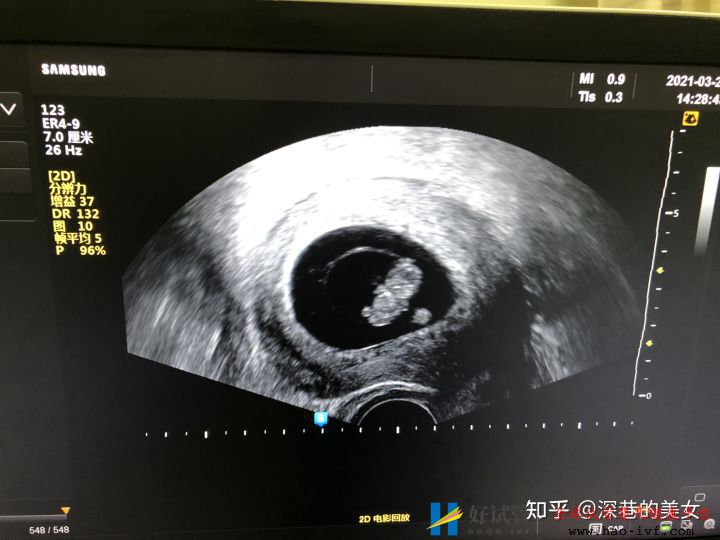

4月8号。目前已经怀孕10周多,宝宝一切都非常好,没有孕吐没有不适。真的是个天使宝宝。多囊如果发现怀孕一定要及时去医院保胎。也希望所有的多囊姐妹能够放下纠结。回归自己。相信大家都会好孕。最后给大家看一下宝宝的第一张照片。